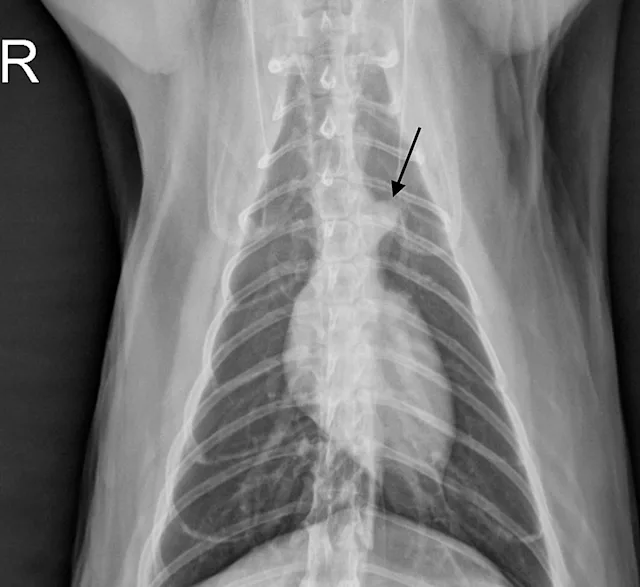

The cardiac silhouette can appear larger in small-breed dogs because the heart occupies a large amount of thoracic space; conversely, the cardiac silhouette can appear smaller in large-breed dogs (eg, greyhounds) due to the relatively larger size of the thorax (Figure 3).2

In dogs and cats, the vertebral heart score (VHS) system measures the width of the cardiac silhouette (ie, distance from cranial to caudal [ie, short axis] along the estimation of where the atria and ventricles meet) and from the carina of the trachea to the apex of the heart at its most ventral point (lines [ie, long axis] should be perpendicular to each other). These measurements are transferred caudally starting at T4 to calculate the VHS (Figure 4).2 Although this measurement is a good general guide, it can be overinterpreted, as cardiac chambers can change size without changing the shape of the cardiac silhouette.3

FIGURE 3A

Relative heart size difference on lateral thoracic radiographs of a normal basset hound (A) and a normal greyhound (B).

The average VHS in dogs is approximately 9.5 ± 0.5 with a normal range of 8.7 to 10.7. The measurement can change based on right or left recumbency (see a compilation of breed-specific VHS reference ranges available from Nguyenba in Suggested Reading). Measurements are more useful when diagnosing dilatative forms of cardiac disease and are reported to be less accurate in dogs with cardiac diseases with concentric hypertrophy.3 VHS for cats in right lateral recumbency is 7.3 ± 0.5.4 A VHS >7.9 has a high diagnostic accuracy in distinguishing cats with left-sided cardiac disorders from healthy cats.5

Because there are breed differences in VHS measurements, finding a reference range is valuable and can increase accuracy of the assessment.3,6 In a study, VHS measurements were found to be most accurate in Yorkshire terriers and Cavalier King Charles spaniels.3 Heart size relative to thoracic volume varies among dog breeds and is considered to be primarily due to thorax conformation. In barrel-chested breeds (eg, bulldogs, Boston terriers, Lhasa apsos), the cardiac:thoracic ratio is generally larger than in normal or deep-chested breeds. The VHS system was developed to help address this issue but its efficacy is unclear (see Benefits & Limitations of Vertebral Heart Scoring).7